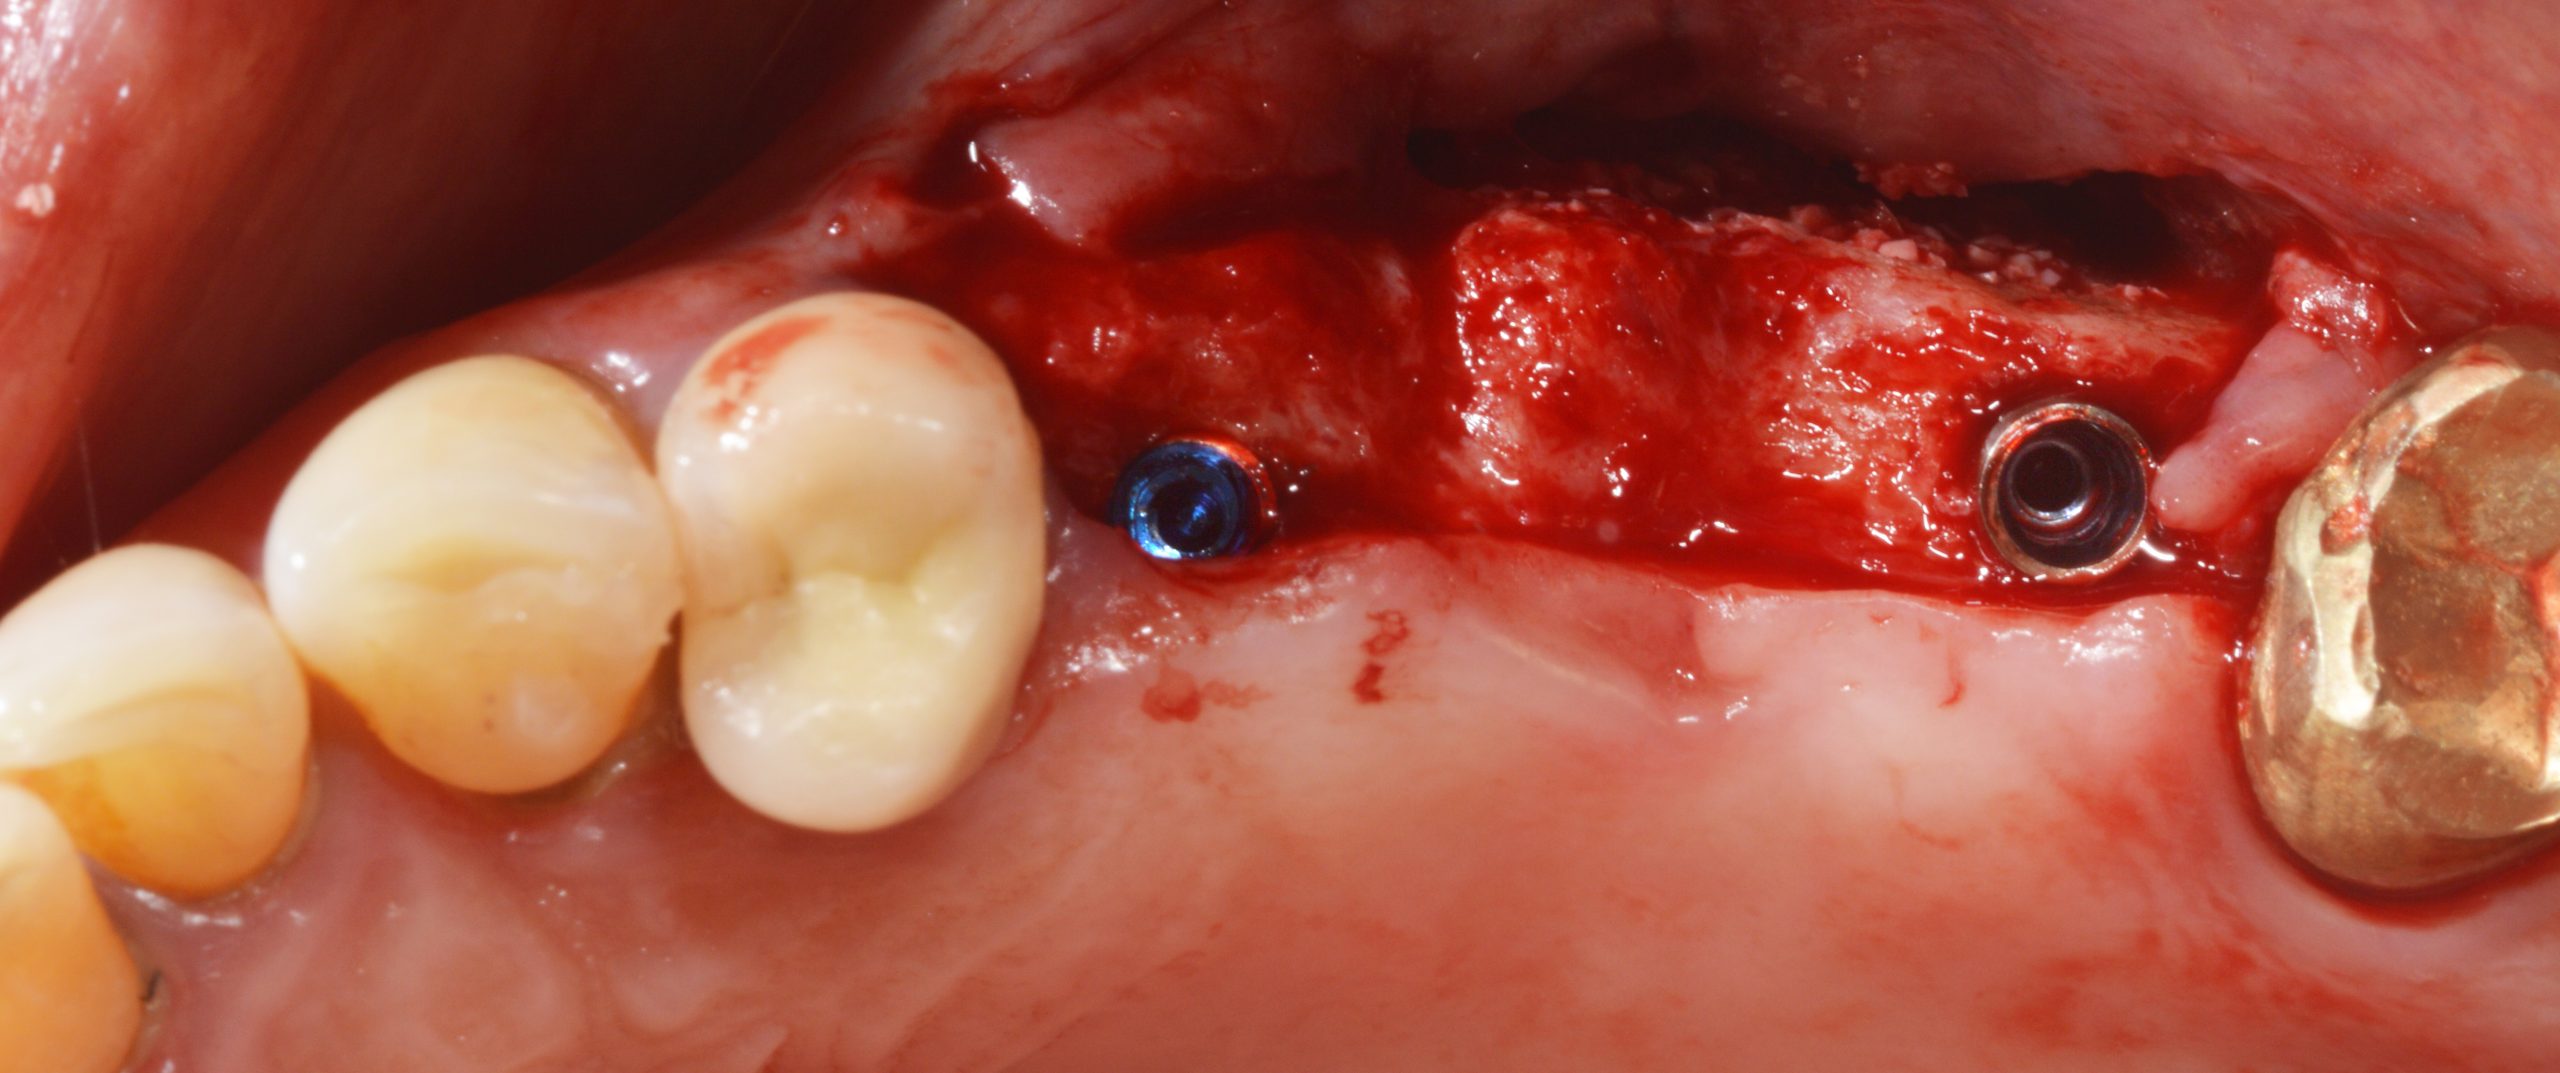

After healing, two 12 mm long BioniQ Plus implants with a 3.5 mm diameter and 1.7 mm high machined neck were inserted and the area was simultaneously augmented with autologous bone and PORESORB-TCP. The augmented area was covered with a collagen membrane (Collagene AT®).

The selection of this type of implant took into account the esthetic characteristics of the upper posterior region.

Postoperative control radiograph: the gingiva former at 24 still needs to be retightened.